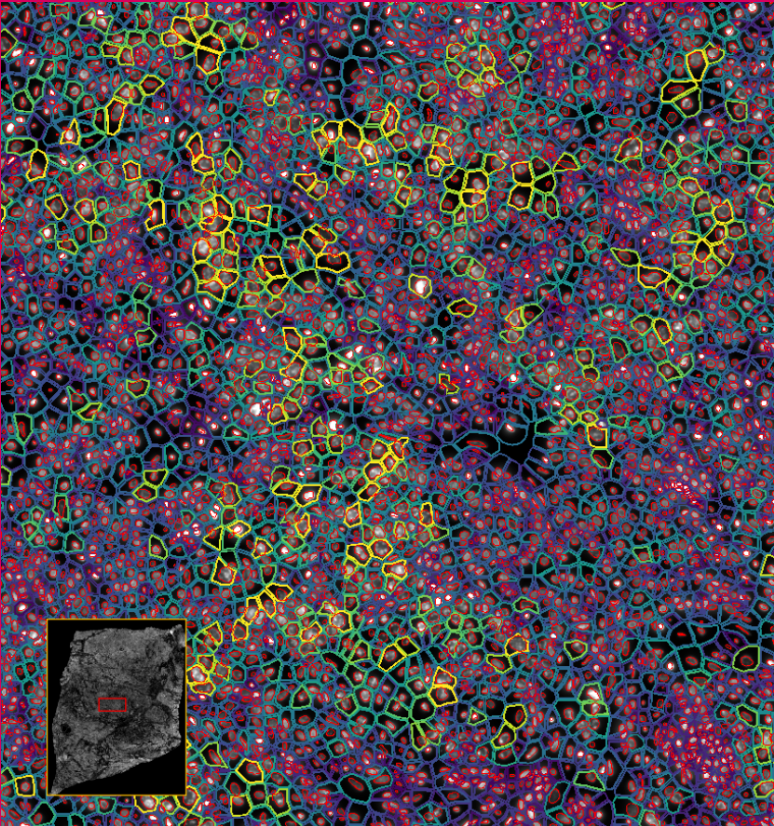

ͼ4-1£ºÊ¹ÓÃDAPI¶Ôϸ°ûºËȾɫ£¬£¬£¬£¬£¬ÍŽáÉî¶ÈѧϰҪÁìÍÆ¶ÏÍêÕûµÄϸ°û½çÏß

ͼ4-2£ºÊ¹ÓÃDAPI¶Ôϸ°ûºËȾɫ£¬£¬£¬£¬£¬ÍŽáÉî¶ÈѧϰҪÁìÍÆ¶ÏÍêÕûµÄϸ°û½çÏß